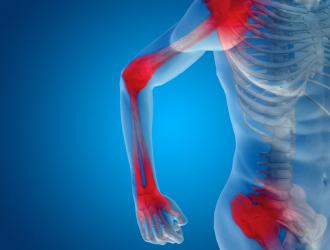

artrite reumatoide

L’artrite reumatoide è la più comune malattia infiammatoria cronica delle articolazioni e anche la più grave. Tante le opzioni terapeutiche, ma nessuna finora risolutiva. I pazienti hanno a disposizione da qualche anno, oltre agli antinfiammatori tradizionali, anche armi terapeutiche potentissime...

Le persone con malattie infiammatorie dell'intestino, diabete di tipo 1 o problemi di coagulazione del sangue possono avere un rischio maggiore di artrite reumatoide.

Mentre le persone con artrite reumatoide sono particolarmente a rischio di sviluppare problemi al cuore e apnea del sonno...